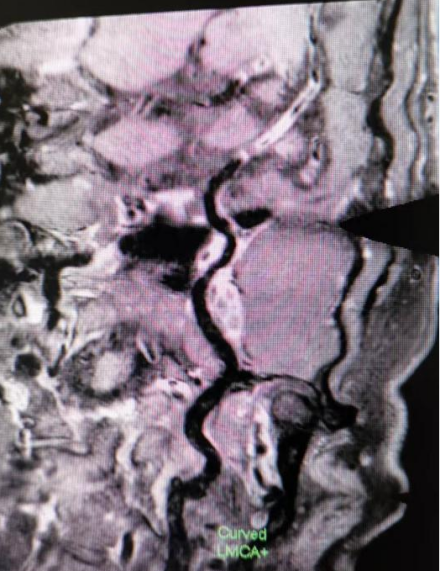

6招丨高危人群的健康(斑块)筛查

d8e1111fe9b857db9a5263342f3650d9.png75171507dca801d3d22214fa0a34ddd3.png

4962a5d190b6d4070e46a59d830b7b26.pnge091ebb0ad3daa65bcf1e30a69dba791.png

通过观察大脑深部穿支动脉如豆纹动脉、内囊动脉开口及管腔情况,可以早期预测发生腔隙性脑梗塞事件的风险。